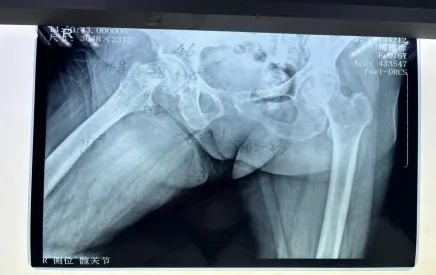

但不幸再次降臨,阿婆在家起床時(shí)不慎摔倒,右髖部疼痛難忍,經(jīng)過醫(yī)院檢查后確認(rèn),傅阿婆為右側(cè)股骨頸骨折。

阿婆住院后,羅院長立馬聯(lián)系內(nèi)科和麻醉科專家來會診,積極調(diào)整阿婆各項(xiàng)不理想指標(biāo),盡量將手術(shù)風(fēng)險(xiǎn)降到最低。羅院長還針對阿婆病情特殊情況進(jìn)行一對一的計(jì)算機(jī)三維精準(zhǔn)規(guī)劃,精心打造出詳細(xì)的手術(shù)方案,經(jīng)過羅院長手術(shù)團(tuán)隊(duì)的努力,阿婆成功完成了機(jī)器人輔助下右側(cè)人工雙動(dòng)股骨頭置換術(shù)。